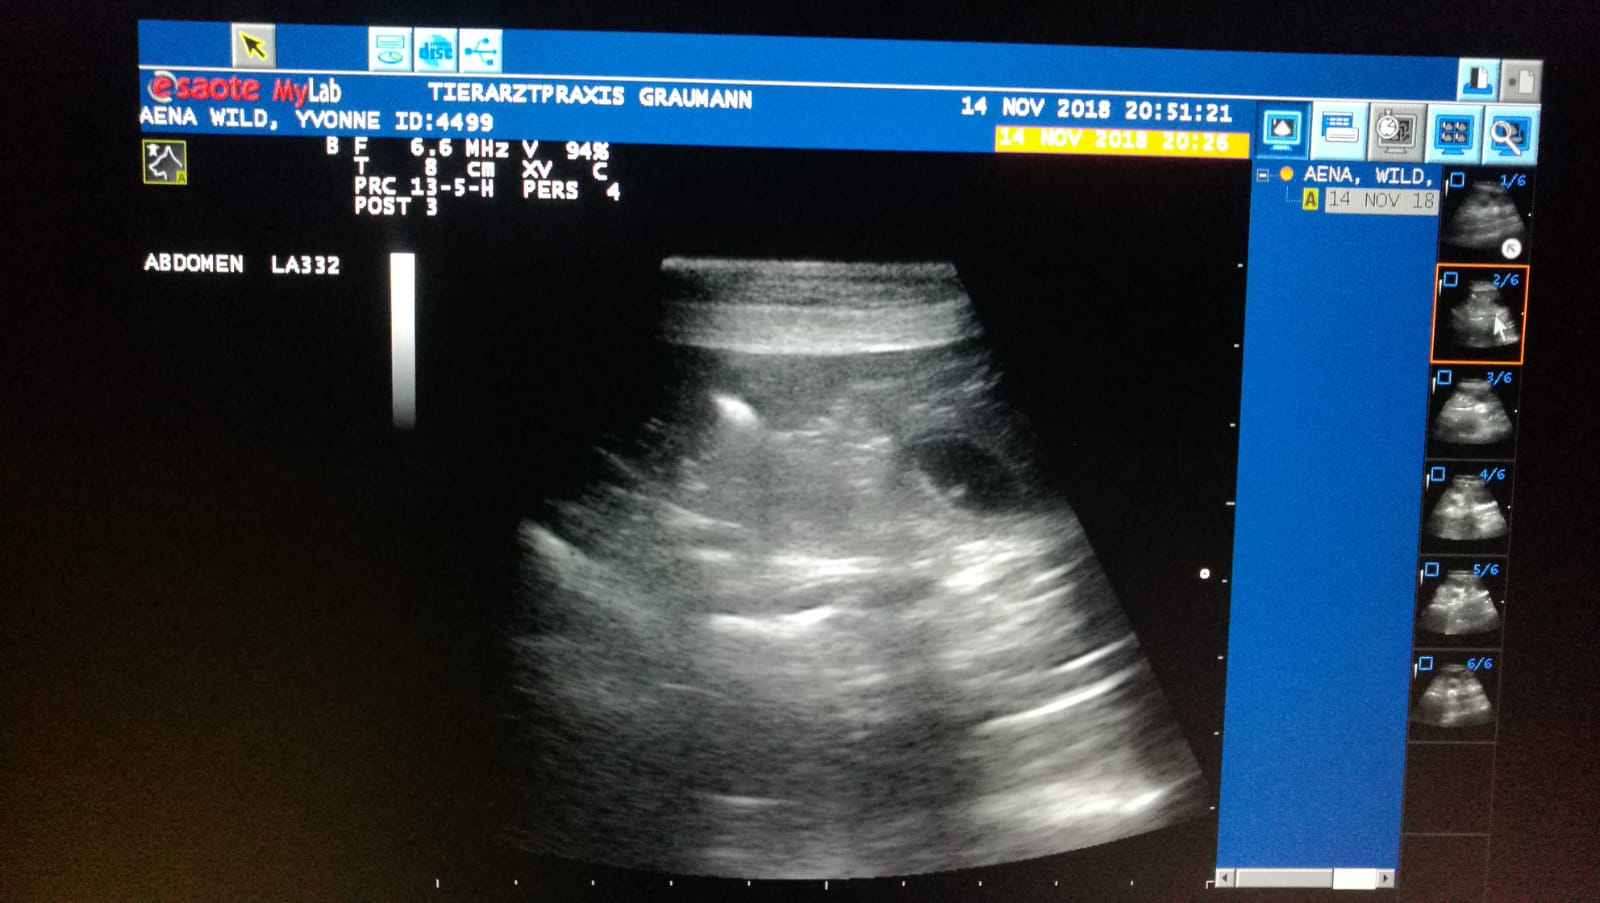

Ultraschall: 5+ Welpen